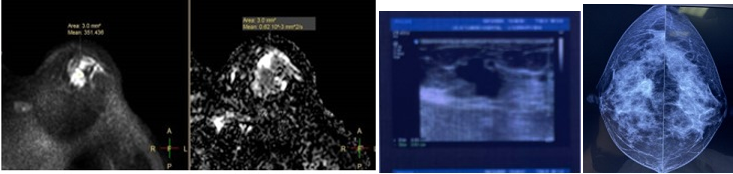

患者,46岁,因“左乳肿物2个月”入院,入院后行相关检查,经查:乳腺核磁及乳房彩超、乳腺钼靶摄像均考虑BI-RADS 4C类,术前肿物穿刺,病理证实为乳腺癌。患者具有非常强烈的保乳愿望,但肿物位于上象限,触诊肿物约为3.5cm,按保乳手术的方法,将肿物扩切后,乳房的上缘及内上缘将不会有腺体保留,因此无法缝合缺损,患者将会出现明显的术后乳房畸形。如果采用目前常用的上象限保乳整形的方法,或导致乳头移位或出现缺损缝合不足,都会导致术后乳房畸形。